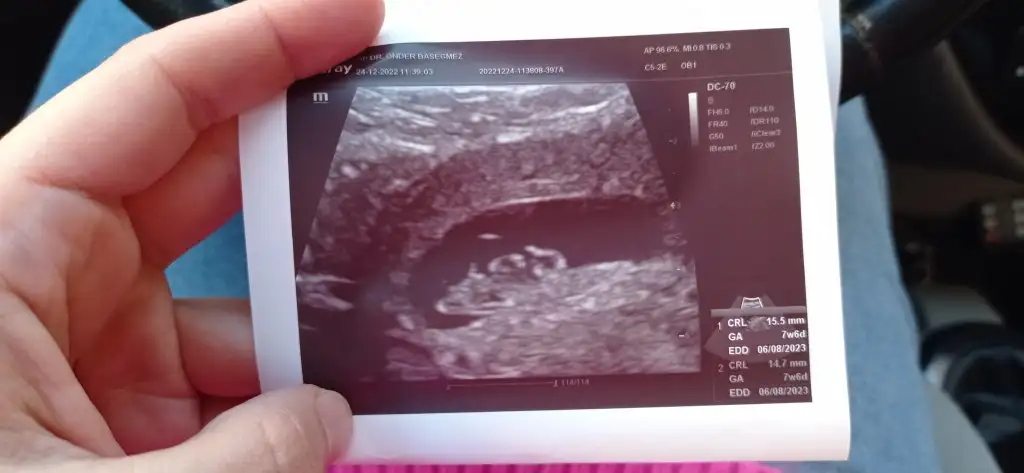

Bize de yorum yapar mısın teyzesi :) Karından ultrason

• IMG_20221224_115456.webp

IMG_20221224_115456.webp

20,5 KB · Görüntüleme: 127